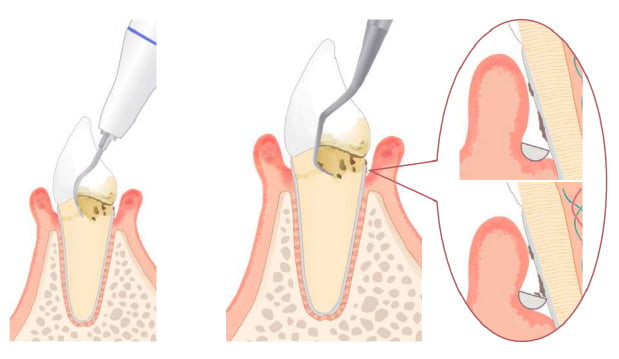

歯周基本治療

超音波スケーラーなどを使ってプラークや歯石を除去します。

-

超音波による歯石除去

大量についた歯石に振動を与えて一気に取り除きます。

SRP

麻酔をして深いポケット内の歯石を除去し、歯根面を清掃していきます。本数が多い場合は、数回に分けて行います。細菌検査で特定の歯周病菌が検出された場合抗生剤を使った薬物療法を行う場合があります。

手作業の器具による細かな部分の仕上げ

深いところや狭い部分についた歯石を丁寧に取り除ききれいにします。